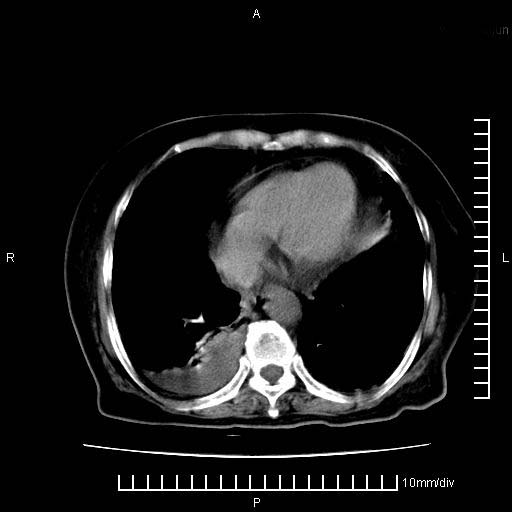

标题: CT28280:腹部增强:女性,80岁

上腹疼痛月余,外院核磁诊断胰腺癌。现临床示右下腹可明显触及包块,可片子上怎么没有看到?

1.胰腺颈体部癌。

2。腹腔积液。

3。右胸腔积液,伴右肺下叶部分萎陷。

4。右肾盂囊肿。

1。胰腺ca伴腹膜腔转移

2。肝左叶低密度灶,考虑转移可能

胰腺结构模糊,胰尾部见囊性包块,周围脂肪密度增高,左肾前筋膜增厚,胸水、腹水。不符合胰腺ca伴腹膜腔转移。考虑胰腺炎伴假性囊肿形成、胸腹腔积液。

1)考虑胰腺癌并胰腺假性囊肿形成。2)肝内低密度灶,不排除转移。3)右肾盂积水。4)腹水。5)右侧胸腔积液并右肺下叶部分膨胀不全。

考虑胰腺ca伴腹膜腔转移、肝左叶转移、右肾积水。右胸腔积液。